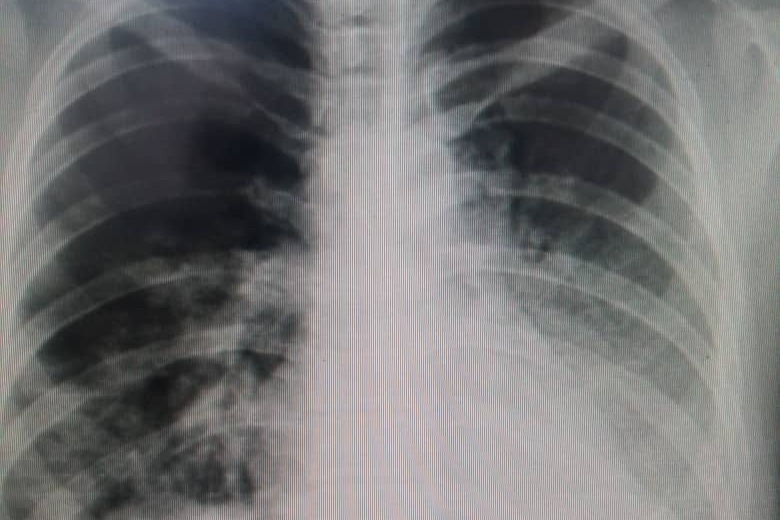

Nohely Pernía es Enfermera y una de los muchos trabajadores de la salud afectados por el Covid-19. Con la grave crisis humanitaria compleja que atraviesa Venezuela, nuestra familia Pernía Azuaje y amigos, se encuentran en la difícil posición de tener que recurrir a ustedes para poder ayudar a Nohe, que a sus tan sólo 26 años, se encuentra en Caracas, luchando contra una neumonía bilateral y depende de nosotros para solventar su situación y continuar apoyando a otros pacientes como es parte de su día a día.

El fin de semana del 27 de marzo intentamos ingresarla a hospitales en Los Teques, porque a duras penas podía respirar debido al dolor y la tos persistente. Hoy se encuentra en el CMDLT (Centro Médico Docente La Trinidad), con mascarilla de oxígeno, requiriendo medicinas tales como Tocilizumab, cuyas 4 ampollas de 200 Mg, pueden llegar a un costo total comprendido entre 2000 y 3000 dólares. Además de costos posteriores adicionales por administrarle oxígeno.

Nohely is a 26 years old Venezuelan Nurse and one of the thousands of health workers affected by Covid-19. With the complex humanitarian crisis that Venezuela is going through, our Pernía Azuaje family is in the difficult position of requesting your help. Currently, she is in Caracas fighting against bilateral pneumonia and depends on us to solve their situation and continue to help patients as part of her everyday life.

On the weekend of March 27th, we tried to ingress her to different hospitals in Los Teques, because she hardly could breathe due to the pain and persistent cough. Currently, she is at CMDLT, with the support of an oxygen mask, requiring different medicines such as Tocilizumab, whose pair of injections can cost between 2000 and 3000 USD. Plus additional subsequent costs for administering oxygen.